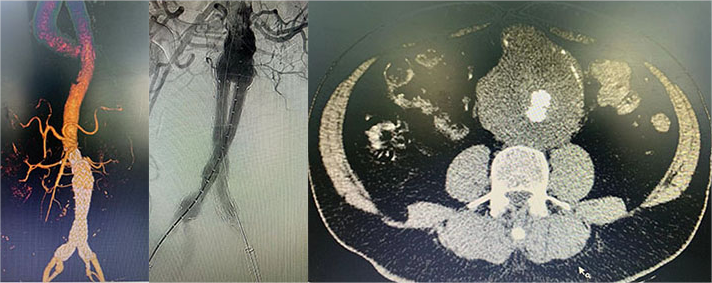

介入血管外科:“原位开窗术”成功救治B型主动脉病变患者

近日,南方医科大学第五附属医院介入血管外科团队独立完成了一例胸主动脉夹层覆膜支架腔内隔绝+原位开窗手术。整个团队经过2小时的努力,顺利完成了手术,患者安全返回病房。 75岁的患者在南方医科大学第五附属医院就诊期间,主动脉CTA提示:主动脉弓部...